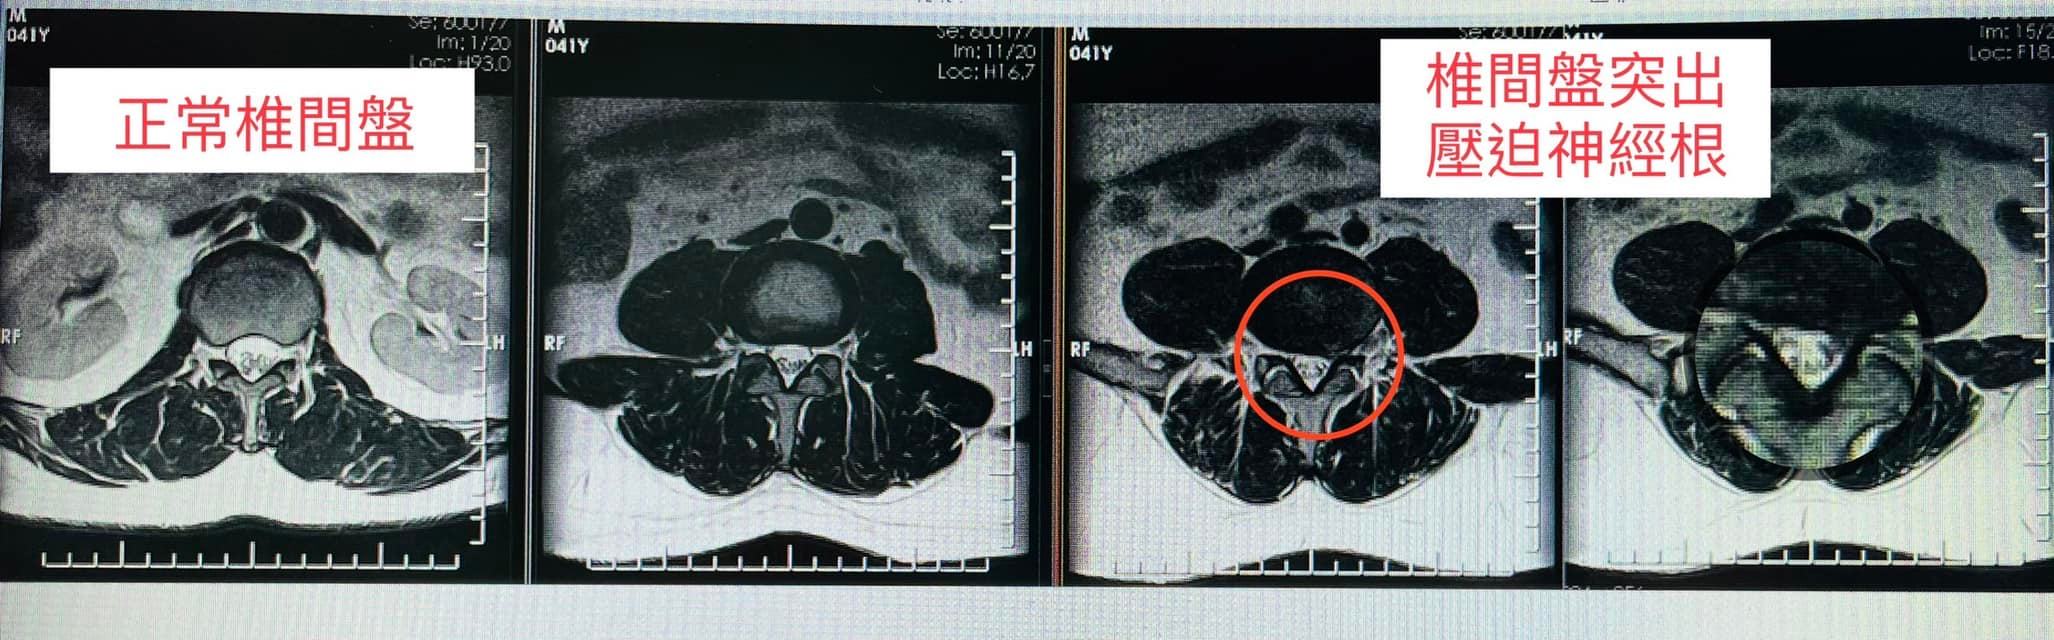

✅拍攝MRI 診斷:

1.左側L 4L5椎間盤突出

2.輕微脊椎側彎

3.梨狀肌症候群